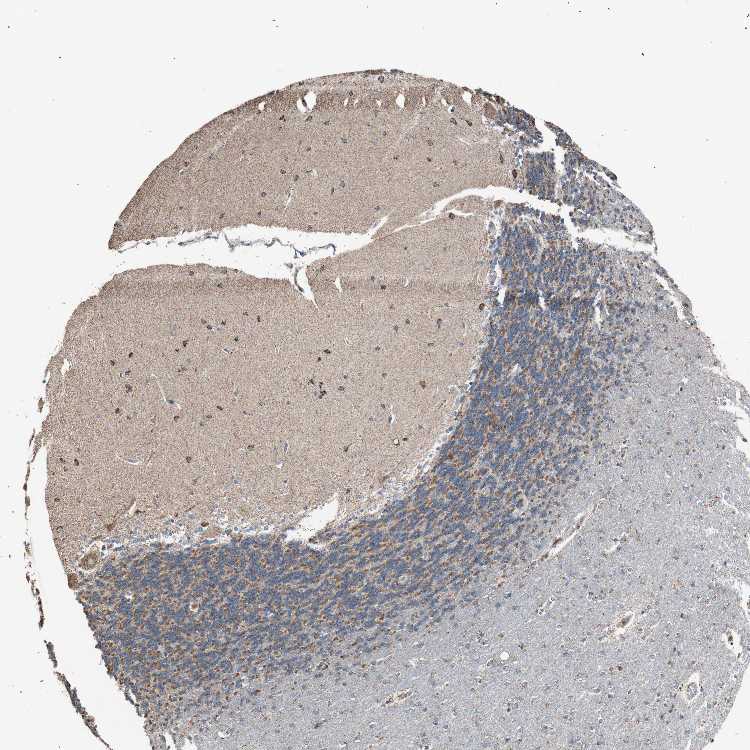

CEREBELLUM - Antibody stainingi

Antibody staining in the annotated cell types in the current human tissue is reported as not detected, low, medium, or high, based on conventional immunohistochemistry profiling in selected tissues. This score is based on the combination of the staining intensity and fraction of stained cells.

Each image is clickable and will lead to virtual microscopy that enables deeper exploration of all samples and also displays staining intensity scores, fraction scores and subcellular localization as well as patient and tissue information for each sample.

Antibody HPA005572

Purkinje cells High

Cells in granular layer Medium

Cells in molecular layer High